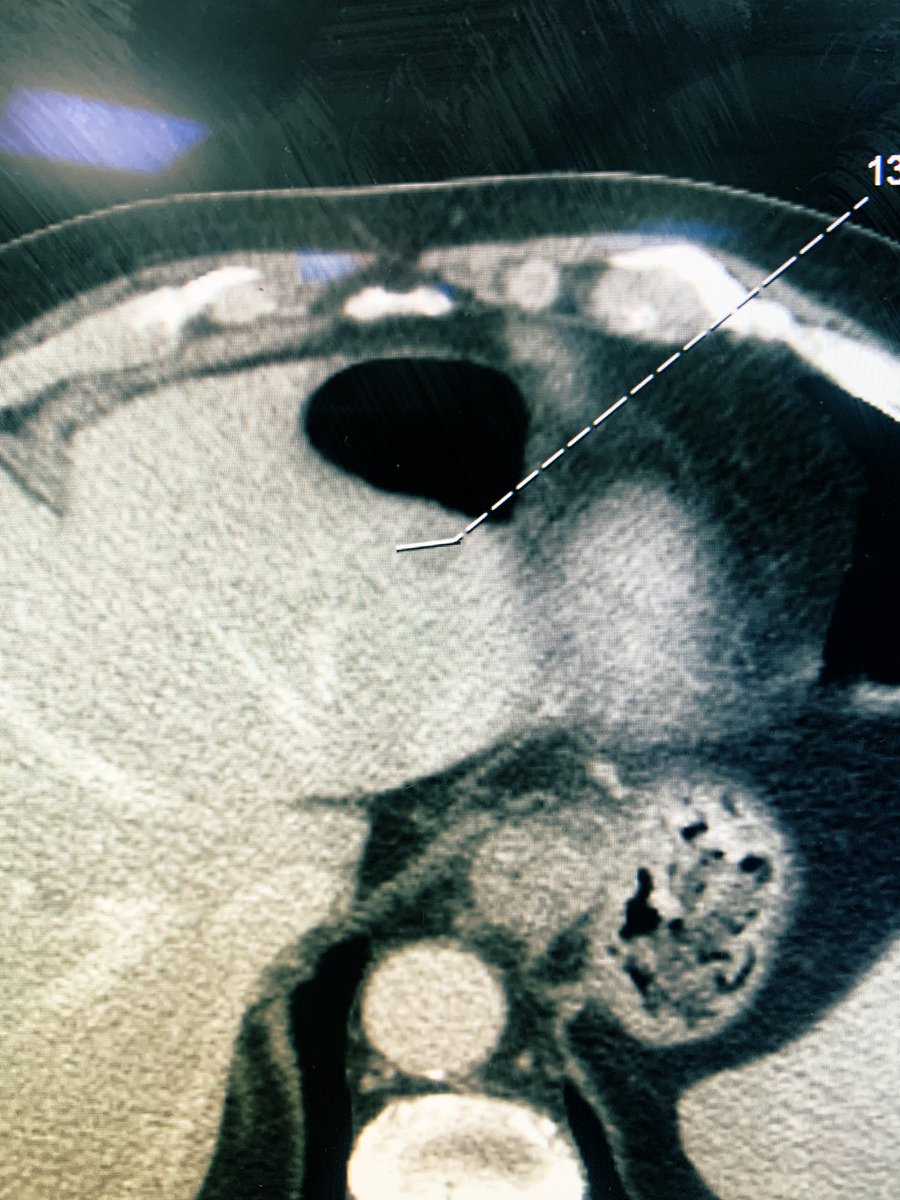

لأول مرة في المملكة، نجح #التخصصي في علاج عدد من المرضى الذين يعانون من انسداد وتضيق الشرايين الطرفية تحت الركبة، باستخدام تقنية مبتكرة تعتمد على إدخال دعامة حديثة تلقائية التحلل عبر قسطرة دقيقة في الفخذ، دون الحاجة إلى جراحة مفتوحة مما أسهم في استعادة تدفق الدم، وتخفيف الألم، وتسريع التئام الجروح، والحد من خطر البتر.